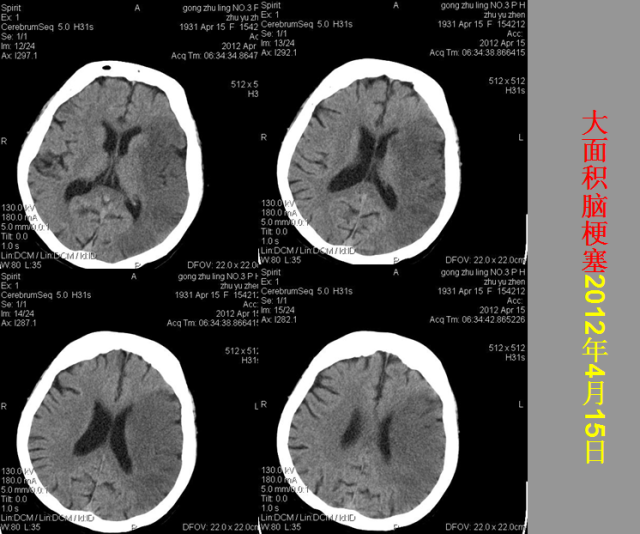

急性颅脑损伤篇